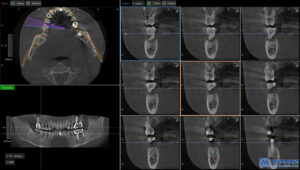

컴퓨터 분석을 통해 미리 계산된

정확한 위치와 각도로 위 사진과 같은

수술 가이드를 제작하고,

가이드를 이용해 임플란트를 심기 때문에

수술 부위의 오차를 줄일 수 있습니다.

가이드는 컴퓨터 분석의 정밀한 계산을 통해

고성능 3D프린터로 제작됩니다.

또한 임플란트를 식립하는 “각도”는

굉장히 중요한 요소인데요.

임플란트의 각도에 따라

임플란트의 안정성과

오래 사용하는 수명이

달라질 수 있습니다.

서울박사치과는 임상경력 많은 의료진과

최신 디지털 장비의 분석을 통해,

식립 각도와 위치를 정밀하게 계산하여

성공률 높은 임플란트 수술을 진행하고 있습니다.